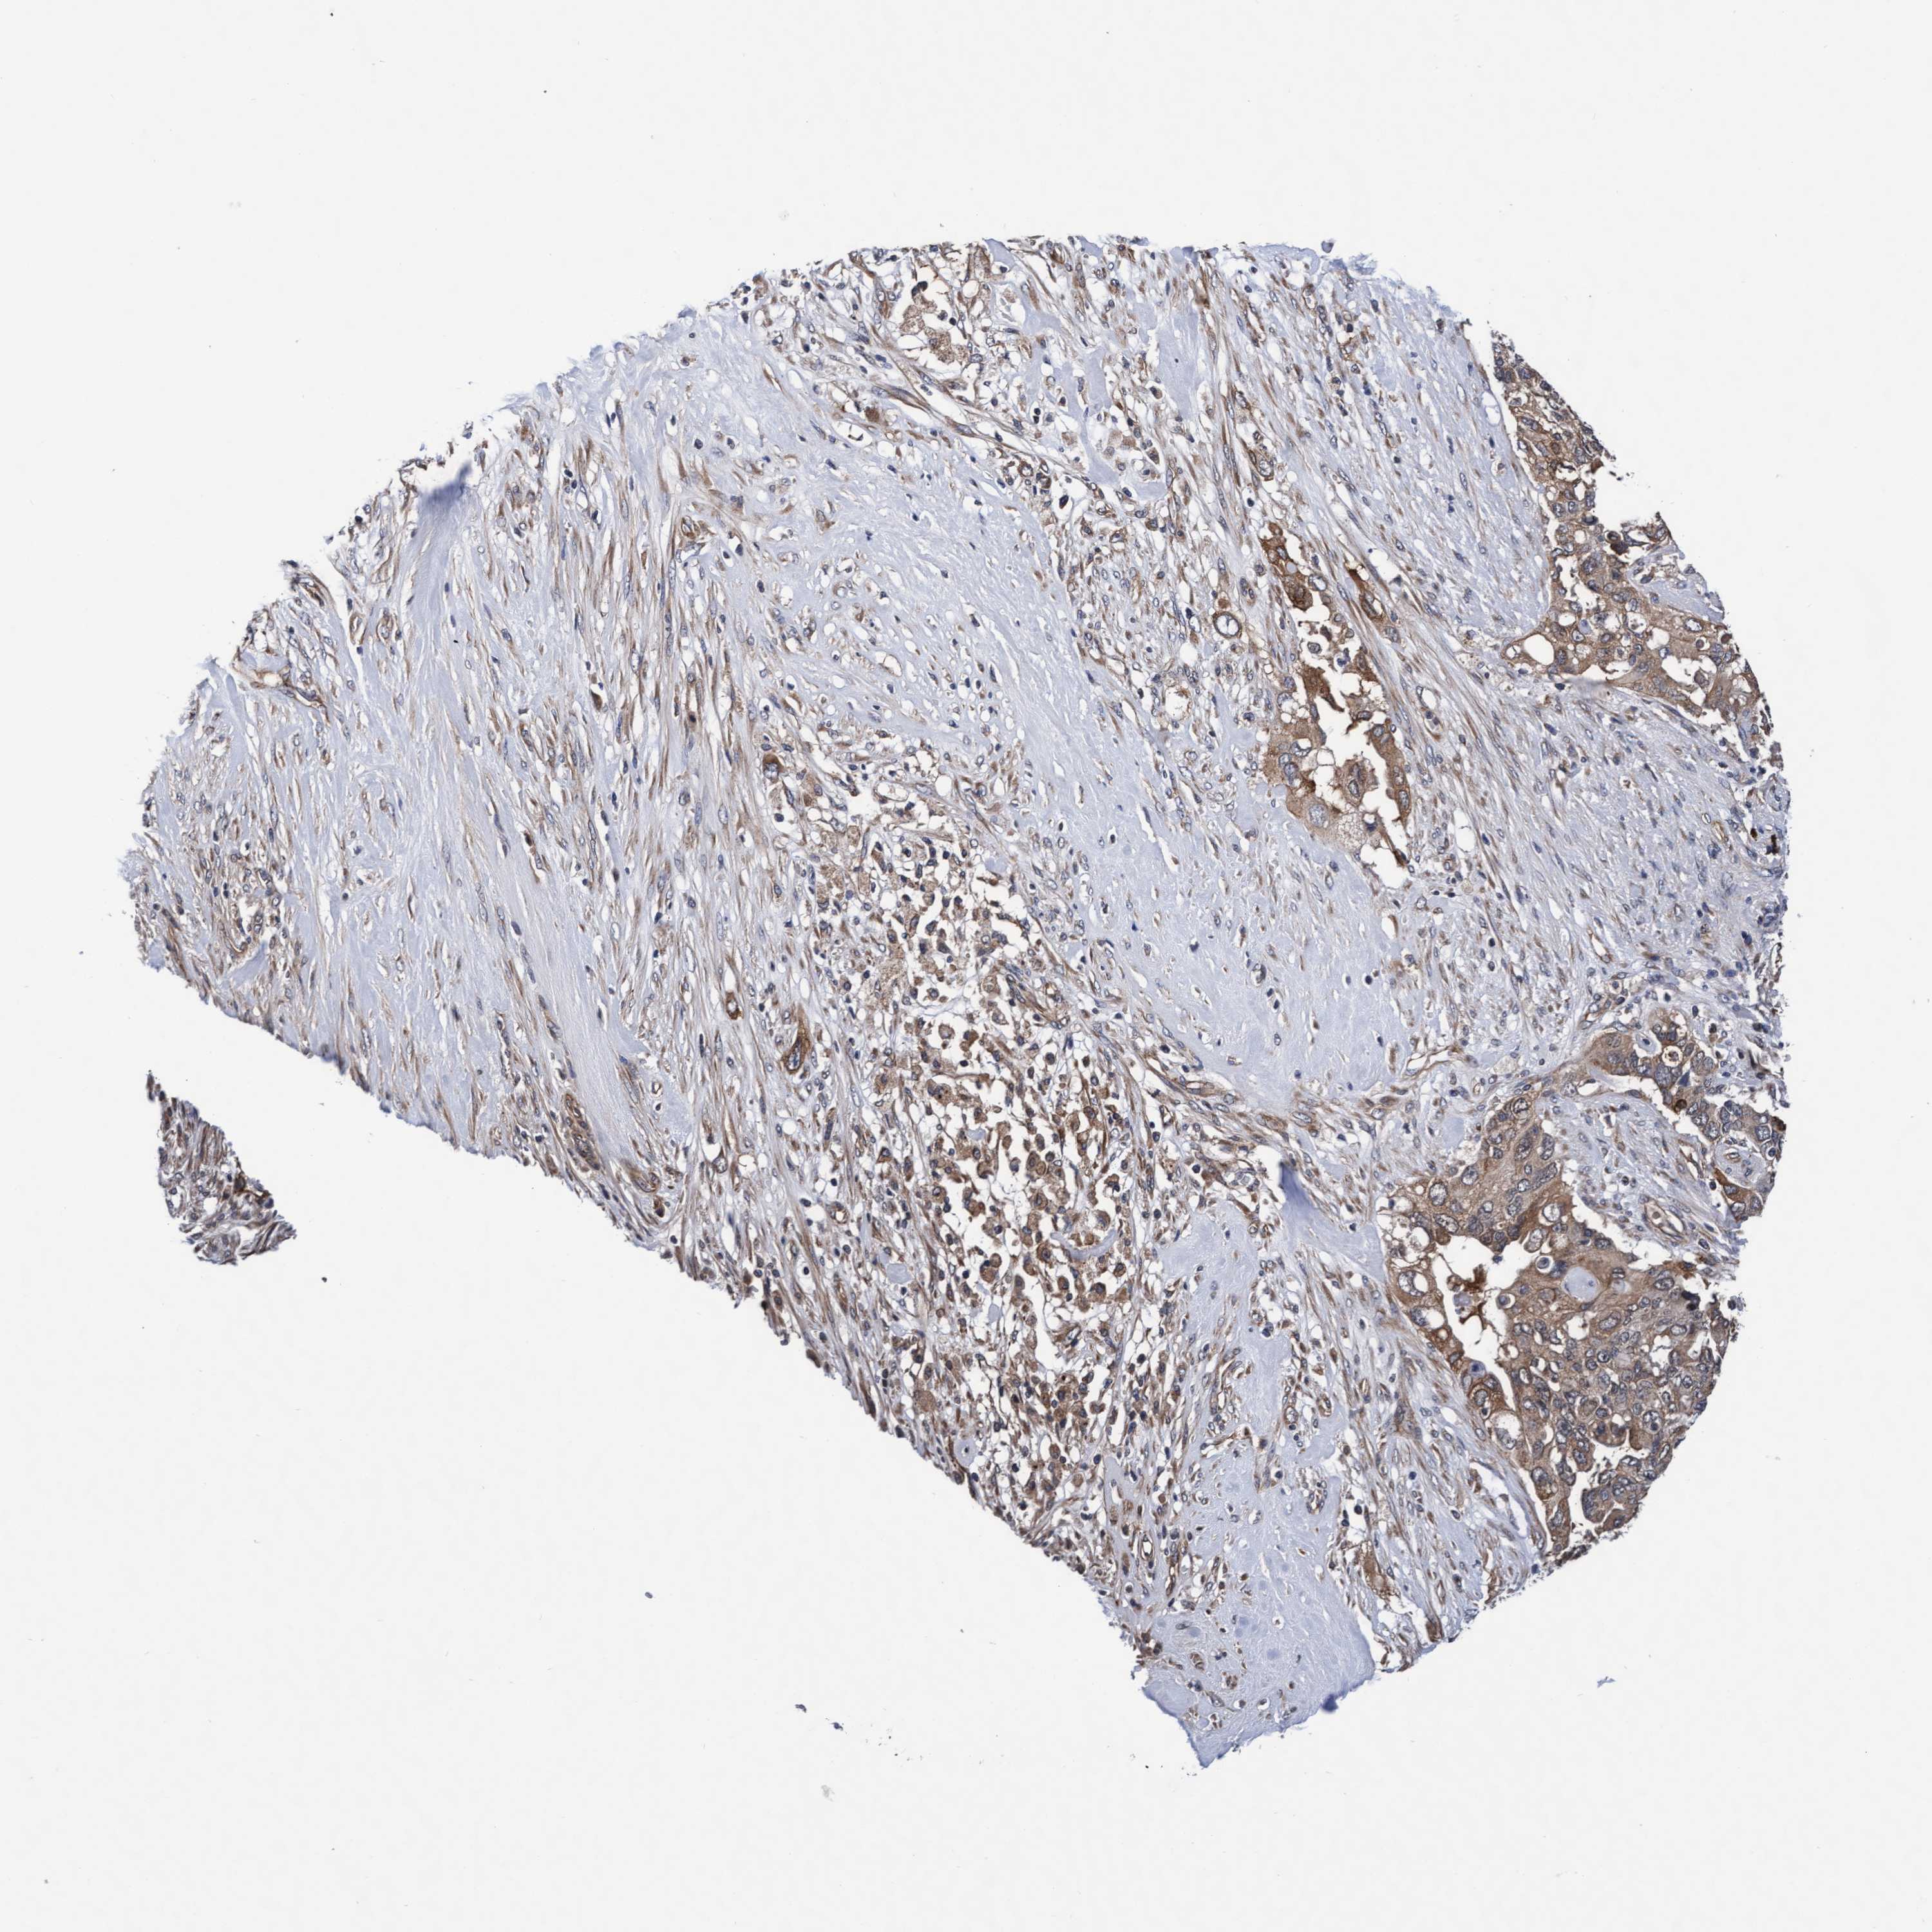

PANCREATIC CANCER - Protein expressioni

A mouse-over function shows sample information and annotation data. Click on an image to view it in a full screen mode. Samples can be filtered based on level of antibody staining by selecting one or several of the following categories: high, medium, low and not detected. The assay and annotation is described here.

Note that samples used for immunohistochemistry by the Human Protein Atlas do not correspond to samples in the TCGA dataset.

Antibody stainingi

Antibody staining in the annotated cell types in the current human tissue is reported as not detected, low, medium, or high, based on conventional immunohistochemistry profiling in selected tissues. This score is based on the combination of the staining intensity and fraction of stained cells.

Each image is clickable and will lead to virtual microscopy that enables deeper exploration of all samples and also displays staining intensity scores, fraction scores and subcellular localization as well as patient and tissue information for each sample.

Antibody HPA021633

Antibody HPA023249

Antibody HPA026561

Antibody CAB002501

Staining

Not detected

Intensity

Negative

Quantity

None

Location

Adenocarcinoma, NOS

Adenocarcinoma, metastatic, NOS